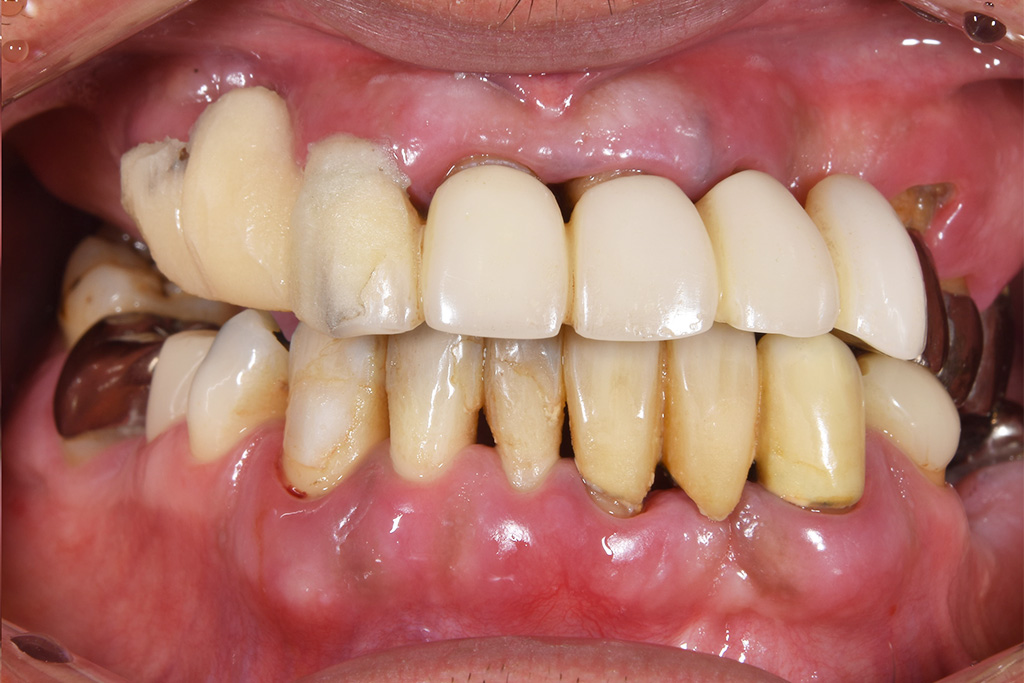

Eさまは重度の歯周病で歯がほぼグラグラな状態でした。

今まで歯の治療をしてはきていたそうですが、その医院ではインプラントをしていなかったため当院のホームページを見て来院されたそうです。

残す歯をどうするか?と考えた時に、インプラントの本数が増えてしまい費用がかなり高額になること、残す歯に不具合が出た場合にまたインプラントの本数が増えてしまことを考えてなるべく費用を抑えたいとのことで、今回はオールオン4治療を選択しました。

Eさまもまたヘビースモーカーのためインプラント治療でのインプラントの定着率の悪さと仕事柄かなり力を使う方なので、抜歯と同時にインプラントを入れて歯まで作るということをしましたが、2本ほどインプラントが定着しませんでした。

そのため6ヶ月で完成のところ、11ヶ月と時間を要してしまいました。

最終の歯が入った後は本当に嬉しくてEさまは泣いていました。

歯というものの重要性を私と共に治療して行く中で思ったそうです。

歯の痛みや違和感を感じたら歯科医院に行くことを周りの人たちに伝えてくれているそうです。